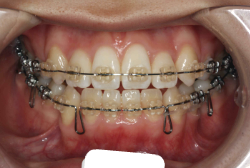

下顎前突・反対咬合

反対咬合とは、歯の生えてくる角度が悪くて下の前歯が上の前歯の外側に出てしまう”歯性反対咬合”と、上下の顎の骨の大きさと形に問題があることで起きる”骨格性反対咬合”に大別されます。骨格的な問題がないか、あったとしても軽度な場合は、大人でも矯正治療で改善することが出来ます。矯正治療のみで治せるのか外科矯正を併用した方が良いのかは、検査診断後に矯正専門医とよく相談して決めていただきます。

初診時の状態ですが、前歯の噛み合わせが逆転していて、下の前歯が外側に来て、上の前歯が裏側になっています。口元の様子ですが、前歯の重なり方が逆なので、唇の様子もそれを反映して、下唇が突出しています。反対咬合としてはかなり重症です。

分析してみると歯の傾き方に問題があるだけでなく、顎の骨の大きさと形にも問題があることが分かりました。ただし、骨の問題点が見つかったからと言って、必ずしも外科矯正になるわけではなく、このくらいの症状ですと、通常の矯正でもきれいに治すことができます。

診断の結果、下の前歯を正しい位置まで内側に入れていくためには、十分な隙間を確保することが避けられないと判断し、上の左右第二小臼歯と下の左右第一小臼歯は抜歯させて頂くことにしました。歯の本数は減りましたが、歯科医学的評価も大きく改善しましたし、審美的にも大幅な改善が見られますね。特に口元の様子が全然変わりました。